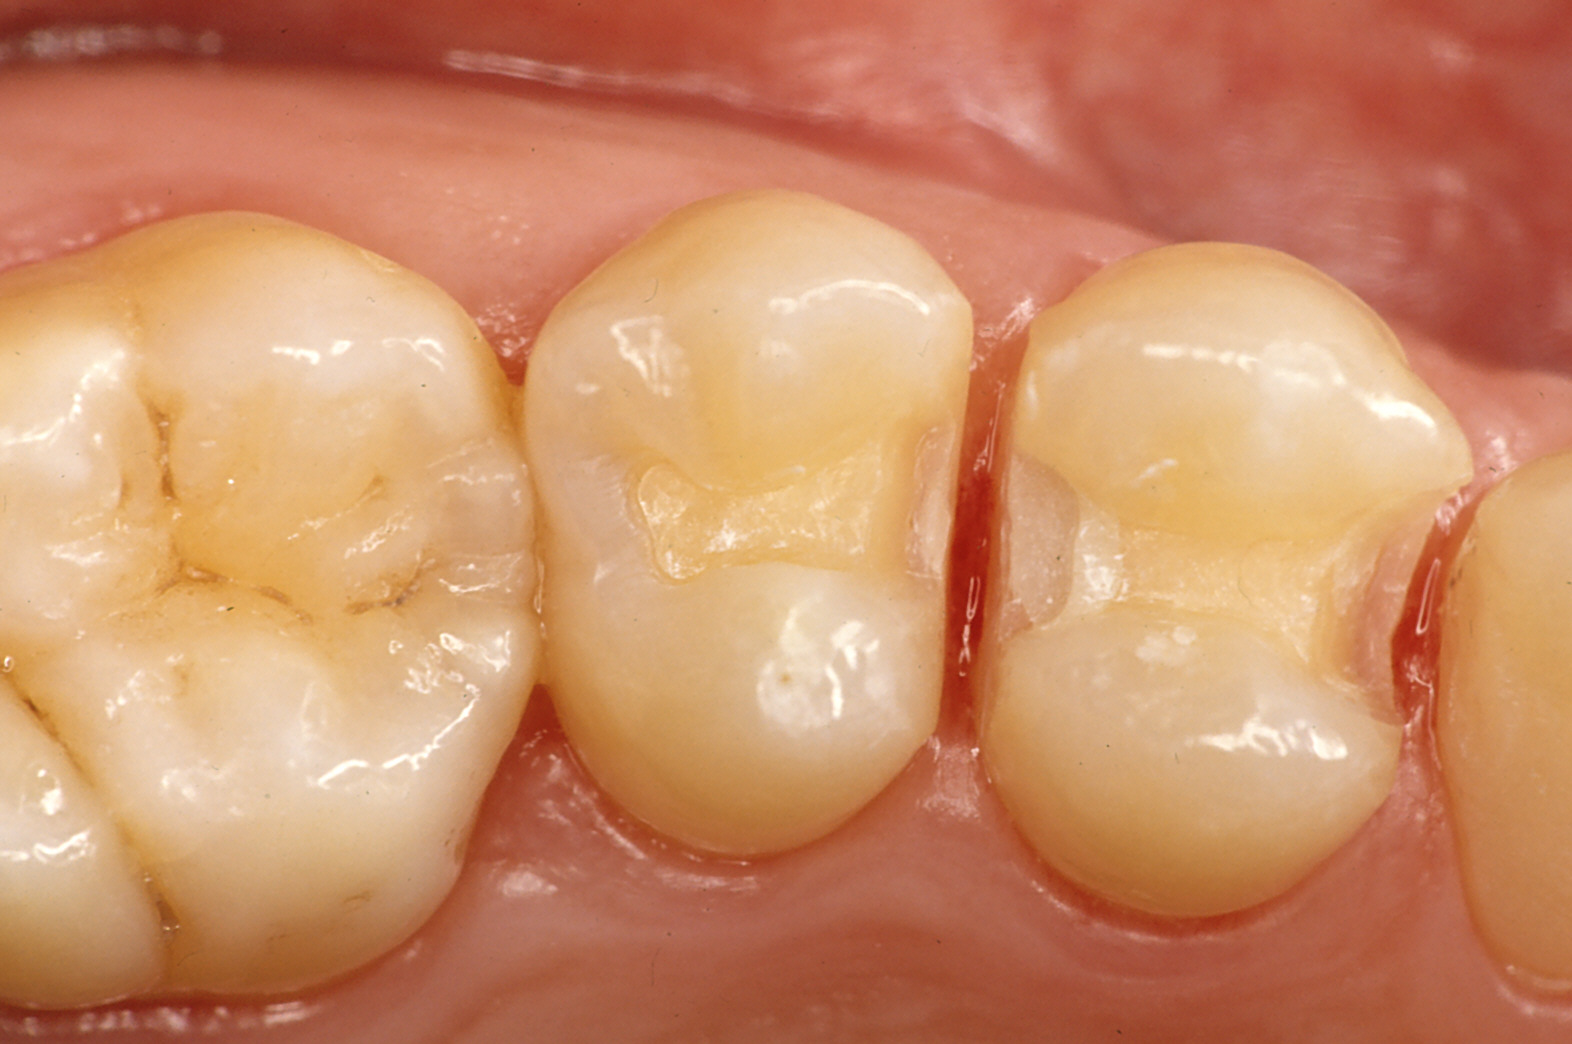

奥歯の治療

上の写真、穴が見えなくても大きな虫歯があります。

(金属で治す場合、下の写真のように削ります)

治療方法

- 金属を入れる

- 保険の白い詰め物で治す

- 保険外(自費)で白い物をはめる(ポーセレンインレー等)

それぞれに利点欠点があります。虫歯の状況だけでなく、かみ合わせ、口腔内環境、習慣等々から総合的に判断しお勧めします。

ワンポイント

白い詰め物、実は、歯と歯肉の境目付近に適応するのは意外に難しいのです。材料、手法を気をつけないと上手く接着せず隙間が生じます。